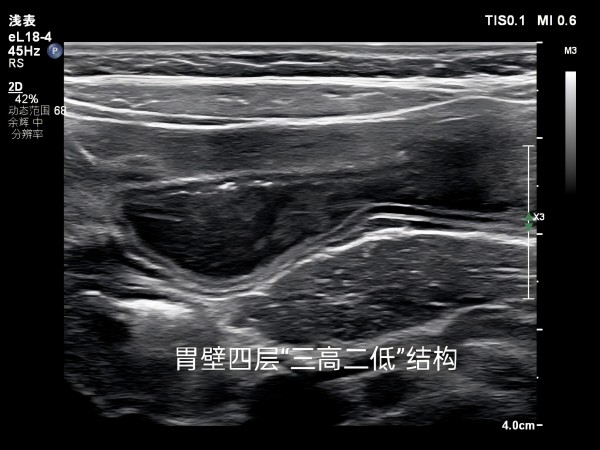

胃十二指肠超声检查项目满足了部分不能进行胃镜、钡餐检查者的需求,图像直观清晰,是一种无创、无痛苦、无损害、操作简便、可重复的检查方法,是胃十二指肠疾病有效的筛选手段。

胃肠道超声检查包括了胃、小肠、大肠的检查,也可以对腹腔内其他一些会引起胃肠道疾病的结构进行检查,例如肠系膜动静脉的先天旋转不良等。